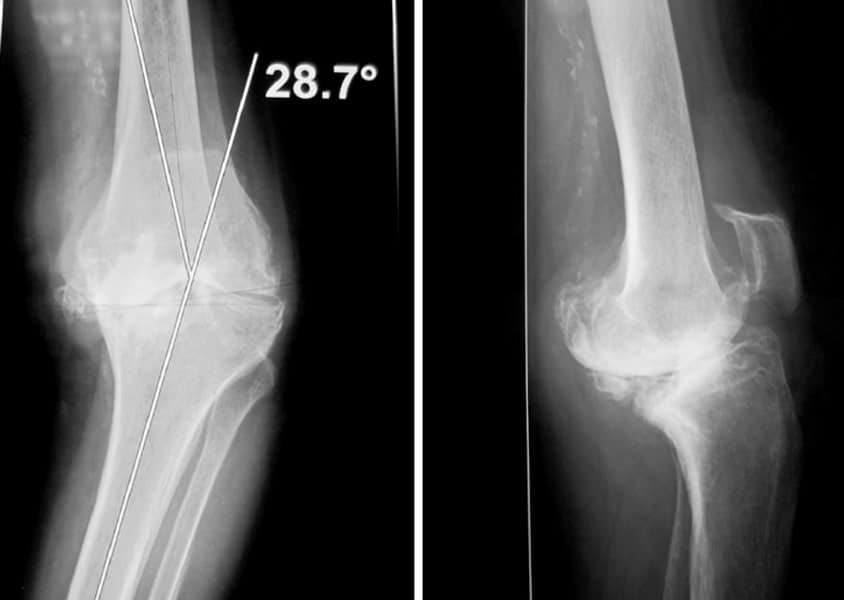

Déformation du genou en valgus (jambes en X), femme jeune (45 ans), ancienne handballeuse aux jeux de Séoul ; le fémur et le tibia sont déformés. Handicap majeur.

On réalise une double ostéotomie de varisation lors de la même opération, fémorale et tibiale, fixées avec des agrafes métalliques.